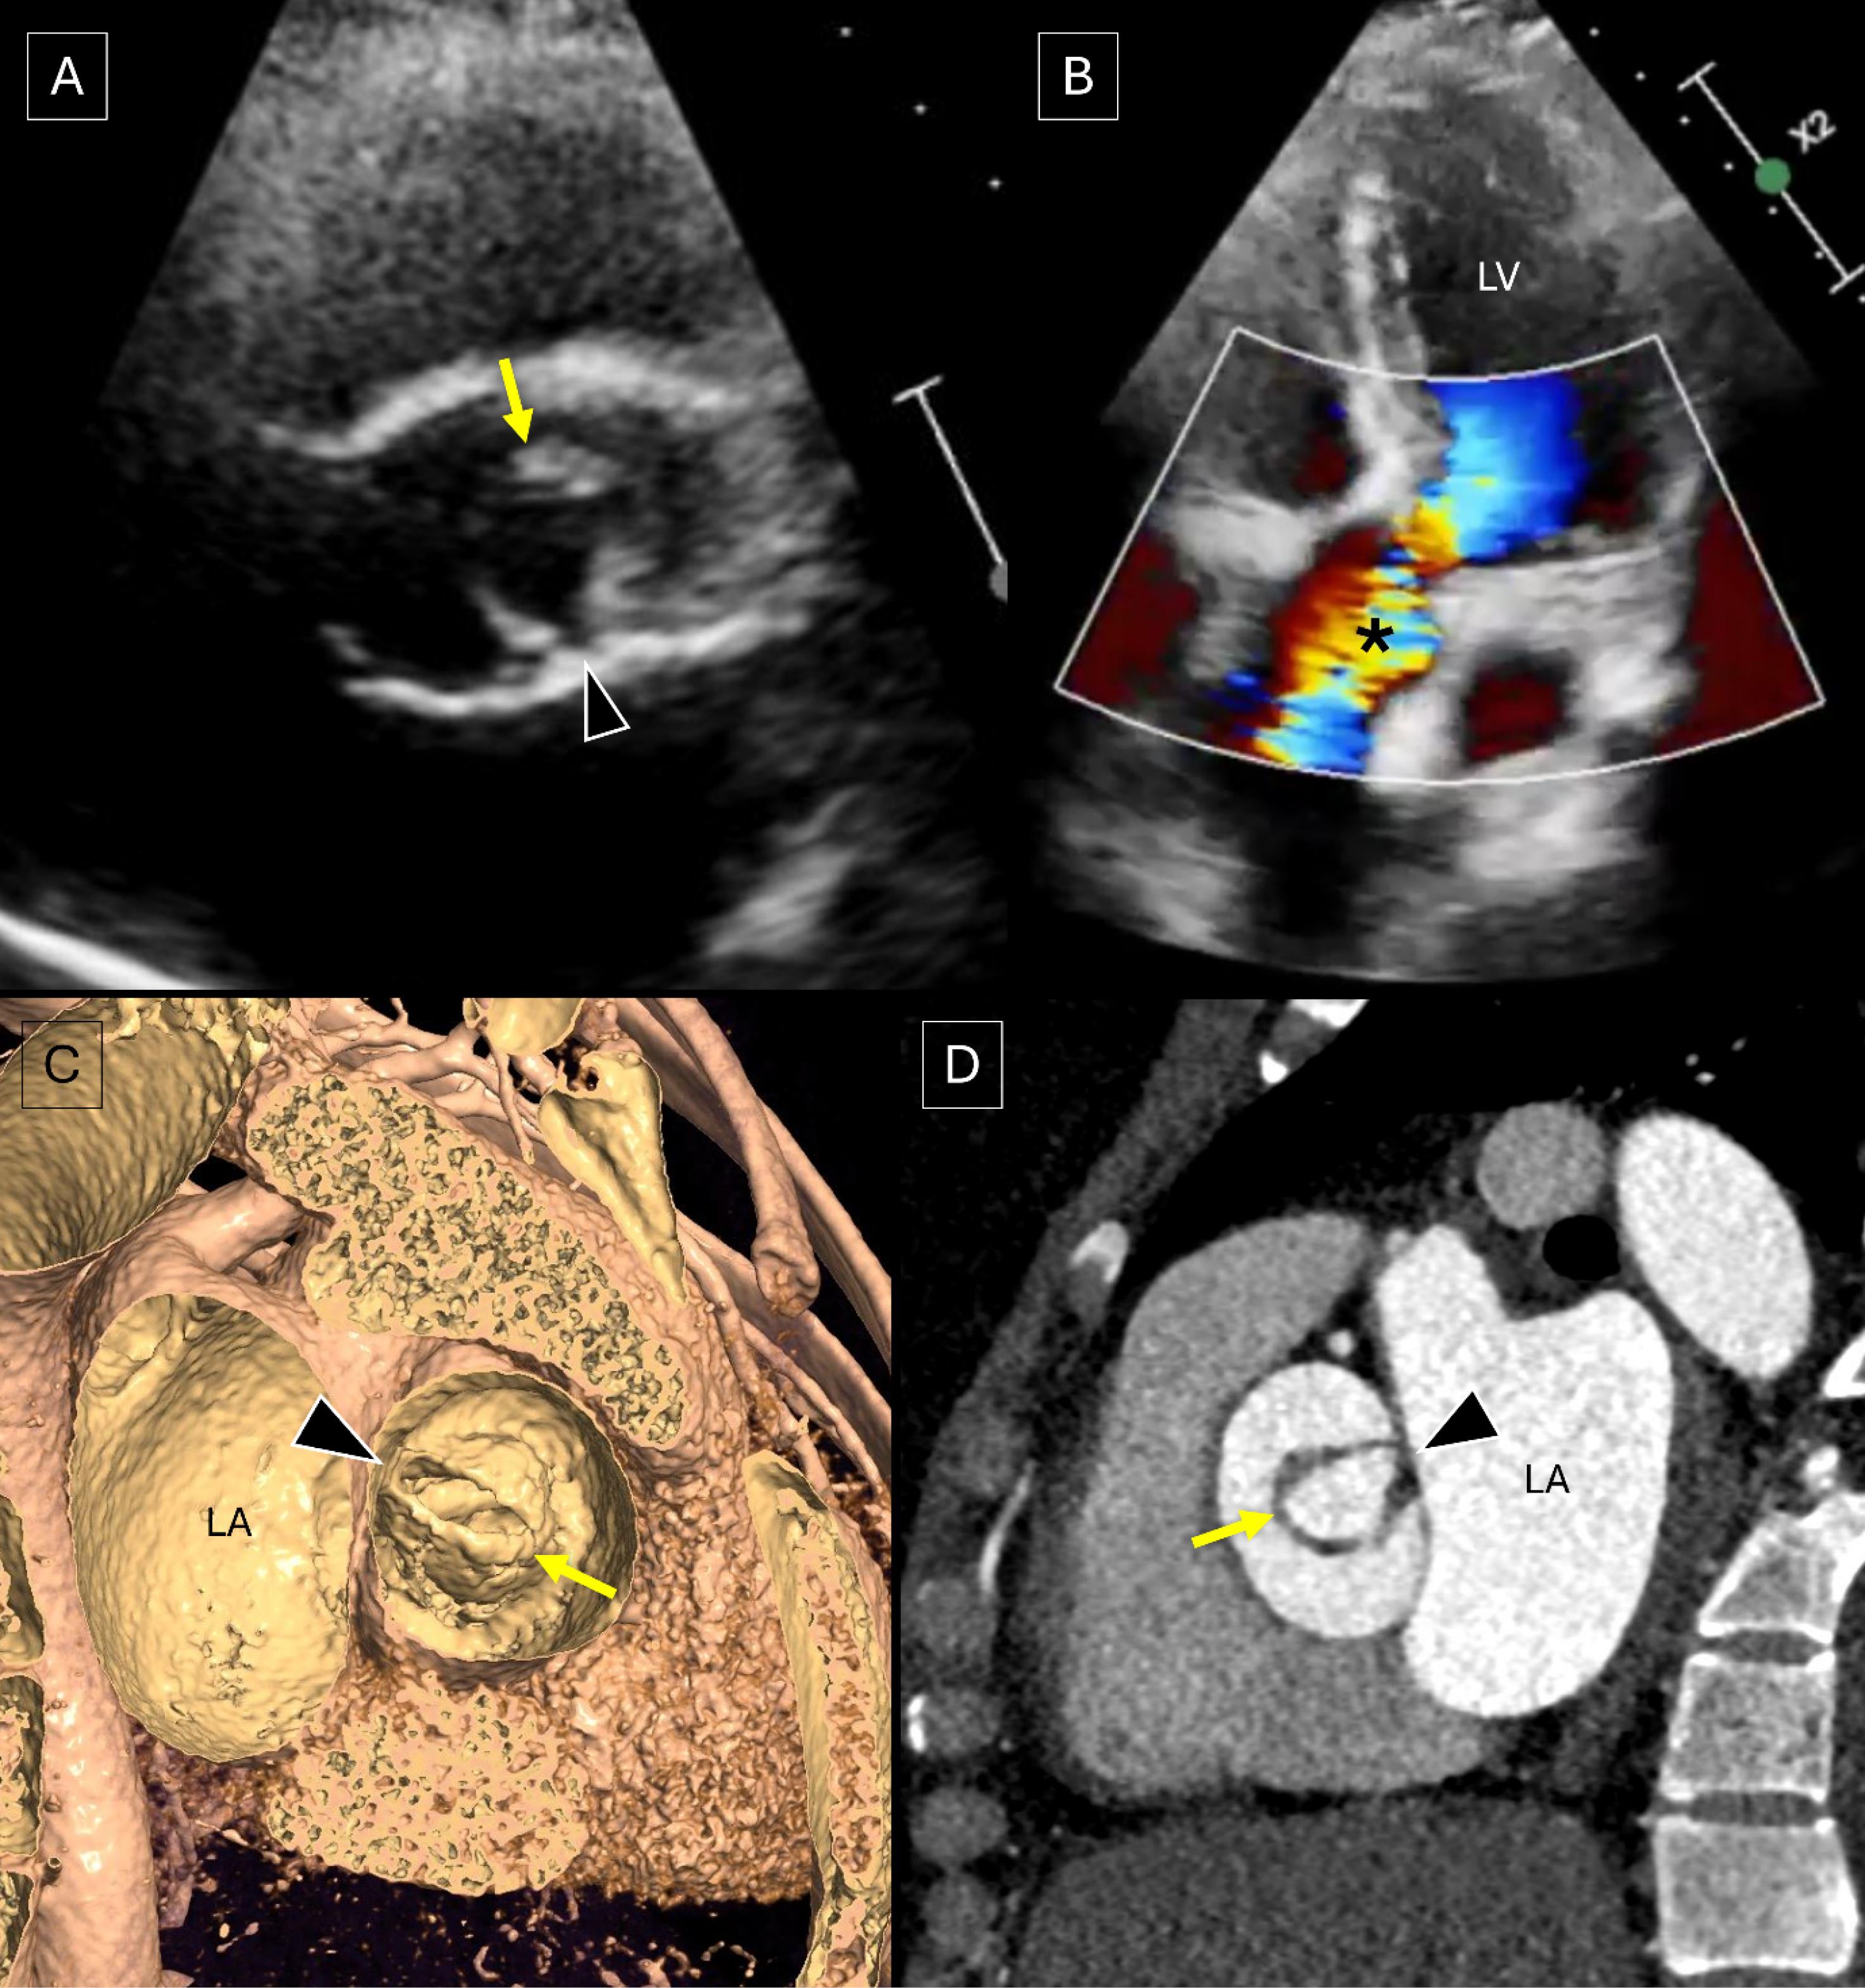

A 30-year-old female presented with gradually increasing dyspnoea on exertion (NYHA II). She had a previous history of undergoing stenting for coarctation of the aorta 1 year back. Transthoracic echocardiography demonstrated the aortic valve having a single commissure, a rounded, leaflet-free edge opposite to the commissure and eccentric valvular opening during systole with severe aortic stenosis (peak gradient of 71 mmHg and mean gradient of 41 mmHg) and normal left ventricular systolic function (Figure 1A-B, Supplementary file 1, video 1 and Supplementary file 2, video 2). A cardiac CT angiography was performed which revealed the aortic valve to be a unicuspid unicommissural valve (Figure 1C-D, Supplementary file 3, video 3). The ascending aorta was dilated (measuring ~ 41 mm in diameter) and the stent across the segment of coarctation was patent (Supplementary file 4, figure S1). Both the coronary arteries were seen arising from a single coronary sinus with adjacent ostia.

Transthoracic echocardiography image of the aortic valve in the short axis plane (A) depicts the aortic valve with a single commissure (arrowhead), a rounded, leaflet-free edge (yellow arrow) opposite to the commissure and eccentric valvular opening during systole. Doppler image in the apical four chamber view (B) reveals eccentric turbulent flow (*) across the aortic valve suggesting aortic stenosis. Virtual dissection image (C) of CT angiography profiling the aortic valve from the ascending aortic side (bird’s eye view) and oblique axial image (D) across the aortic valve demonstrate a unicuspid aortic valve with a single commissure (arrowhead) and an opposite rounded, leaflet-free edge (yellow arrow). [LA: left atrium; LV: left ventricle]